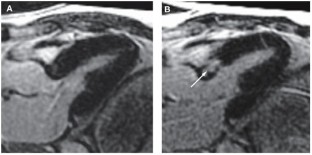

Management Coil embolization of the first two septal vessels resulted in a limited septal infarct (creatine kinase-MB 36.6 µg/l; troponin T 0.43 µg/l) that corresponded to a mass of 8.1 g on gadolinium contrast cardiac MRI. The LVOTG decreased immediately from 78 mmHg to 35 mmHg. On pressure–volume loops, contractile isovolemic and systolic ejectional parameters decreased, while an improvement in diastolic left ventricular function was observed.